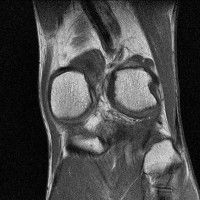

무릎 mri 간단히 봐주실 수 있으시나요 ㅠㅠ

안녕하세요 8년전 십자인대 수술하고 최근 무리한 운동에 무릎 불편감이 생겨서

mri 찍었습니다.

진단결과는 첫 찍은 병원에서 활액막염 이라는 진단을 받았습니다. 혹시 봐주실 수 있으실까요?

올라온 MRI가 단편적이라서 정확한 진단에 어려움이 있지만 십자인대에는 큰 이상이 있지는 않은것 같으며, 무릎관절내 물이 있는 것으로 보아 활액막염의 진단이 맞을 것 같습니다.

하지만 단편적인 영상이기 때문에 촬영병원에서 정확한 판독지 등을 받으시는 것이 좋겠습니다.